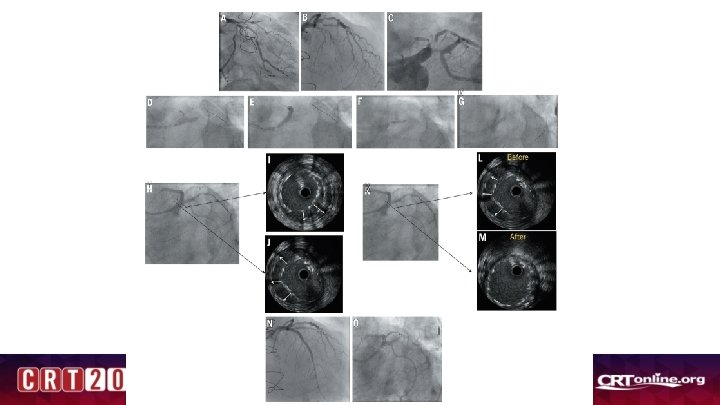

Single vs. Double Kissing Crush Techniques for Left Main Coronary Stenting: Step-by-Step Comparisons of the above techniques by Serial High- Definition Intravascular Ultrasound Examinations

A 1 Baseline angiogram A 2 Crush the SB stent A 3 1 B MV balloon SB stenting B 1 1 C A 4 Opening SB stent Struts B 2 1 D 1 E 1 E 1 st KBI B 3 1 G 1 F LAD B 4 L main Fig. 1 1 H

MV stenting A 1 ST POT B FKBI C LMCA Fig. 2 2 nd POT D